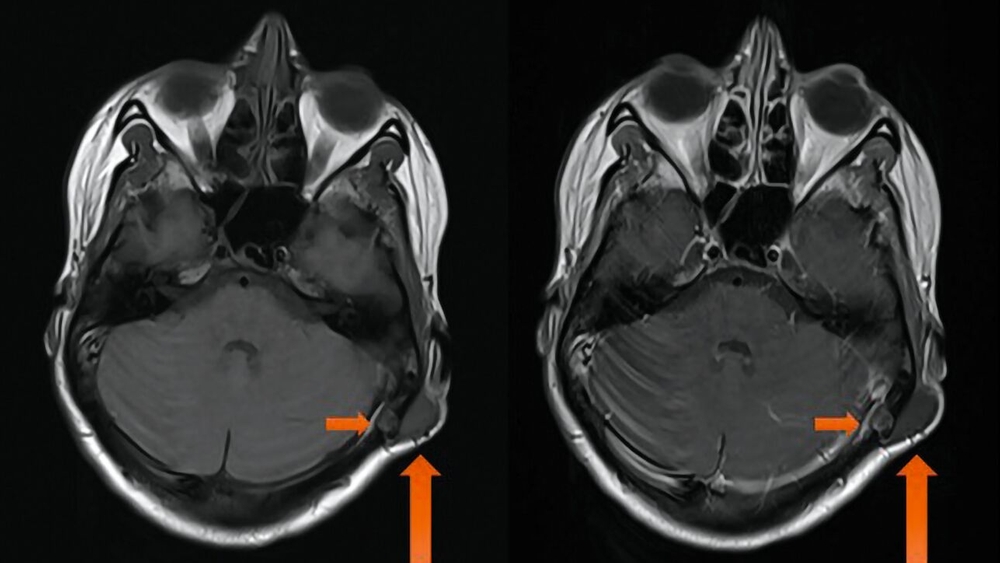

In den vergangenen 18 Monaten war die Raumforderung stark größenprogredient, sodass die Patientin ihren Hausarzt aufsuchte. Dieser veranlasste eine Magnetresonanztomografie, mit der eine 3,5 cm x 1,0 cm x 3,0 cm große subkutane Strukturvermehrung retroaurikulär links mit breitbasigem Kontakt zur Schädelkalotte extrakraniell dargestellt werden konnte (Abbildungen 1 bis 3). Weiter zeigte sich intrakraniell eine noduläre Läsion der Schädelkalotte mit einer Größe von 0,9 cm x 0,8 cm mit einer Impression des linken Sinusknies, die in erster Linie als zystoide Komponente derselben Raumforderung zu werten ist und mit dem extrakraniellen Befund über einen Fistelgang kommuniziert. In der Gesamtbeurteilung wurde der Verdacht einer Epidermoidzyste mit intrakranieller Ausdehnung gestellt. Es folgte die Überweisung an einen niedergelassenen Mund-, Kiefer- und Gesichtschirurgen, der aufgrund der intrakallotären Beteiligung eine Überweisung ins Universitätsklinikum Aachen veranlasste.